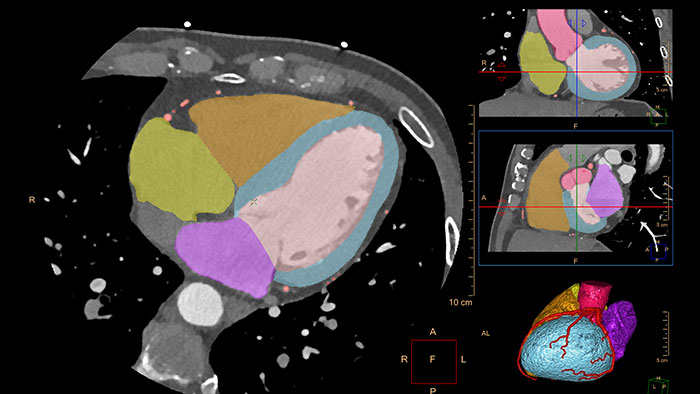

Comprehensive cardiac analysis

Designed to assist the user in viewing, analyzing and quantifying dedicated Cardiac CT Angiograms, mainly for coronary arteries analysis on Coronaries CT Angiogram (CCTA) data.

Assessing myocardial defects

Relies on the automatic 3D model-based whole-heart segmentation from the CCA application to provide visual and quantitative assessment of segmented, low-attenuation areas within the left ventricle myocardium from a single, gated cardiac CTA scan.